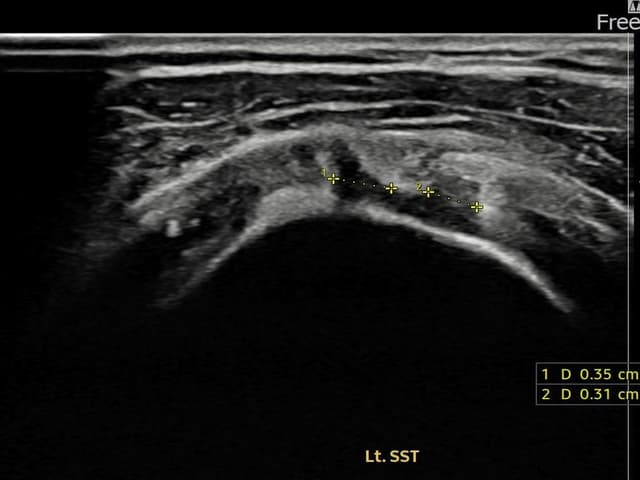

[経過期間: 24.01.08~24.03.14]

[縫縮術] 超音波検査にて左 棘上筋腱 関節面側部分断裂(3.5mm × 3.1mm (부분파열))を確認。縫縮術施行後、腱の連続性が回復し、日常生活に復帰されました。